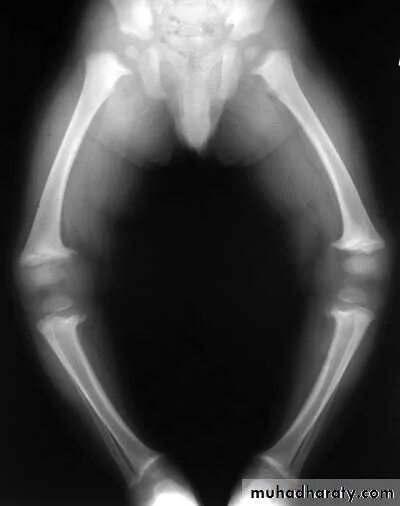

Рахит 6 лет